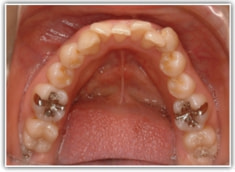

上顎前突ケース

治療法:表の矯正(T21ブラケット)

治療後(2年後)